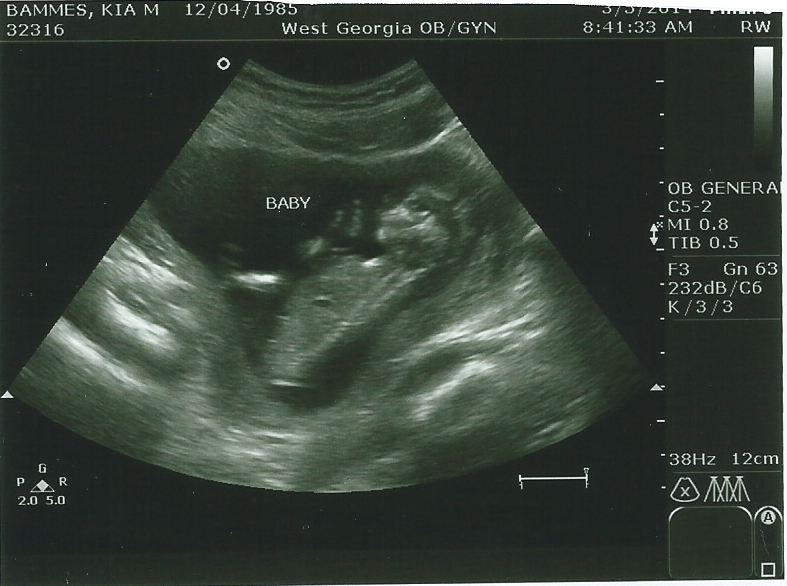

Expecting my first child in August. These are my only ultrasound pics so I'm hoping you guys can help me predict the gender via nub or skull theory. Please share your guesses and why you chose B or G. I'm trying to sharpen my prediction skills. Thanks in advance!

Attachment 17449